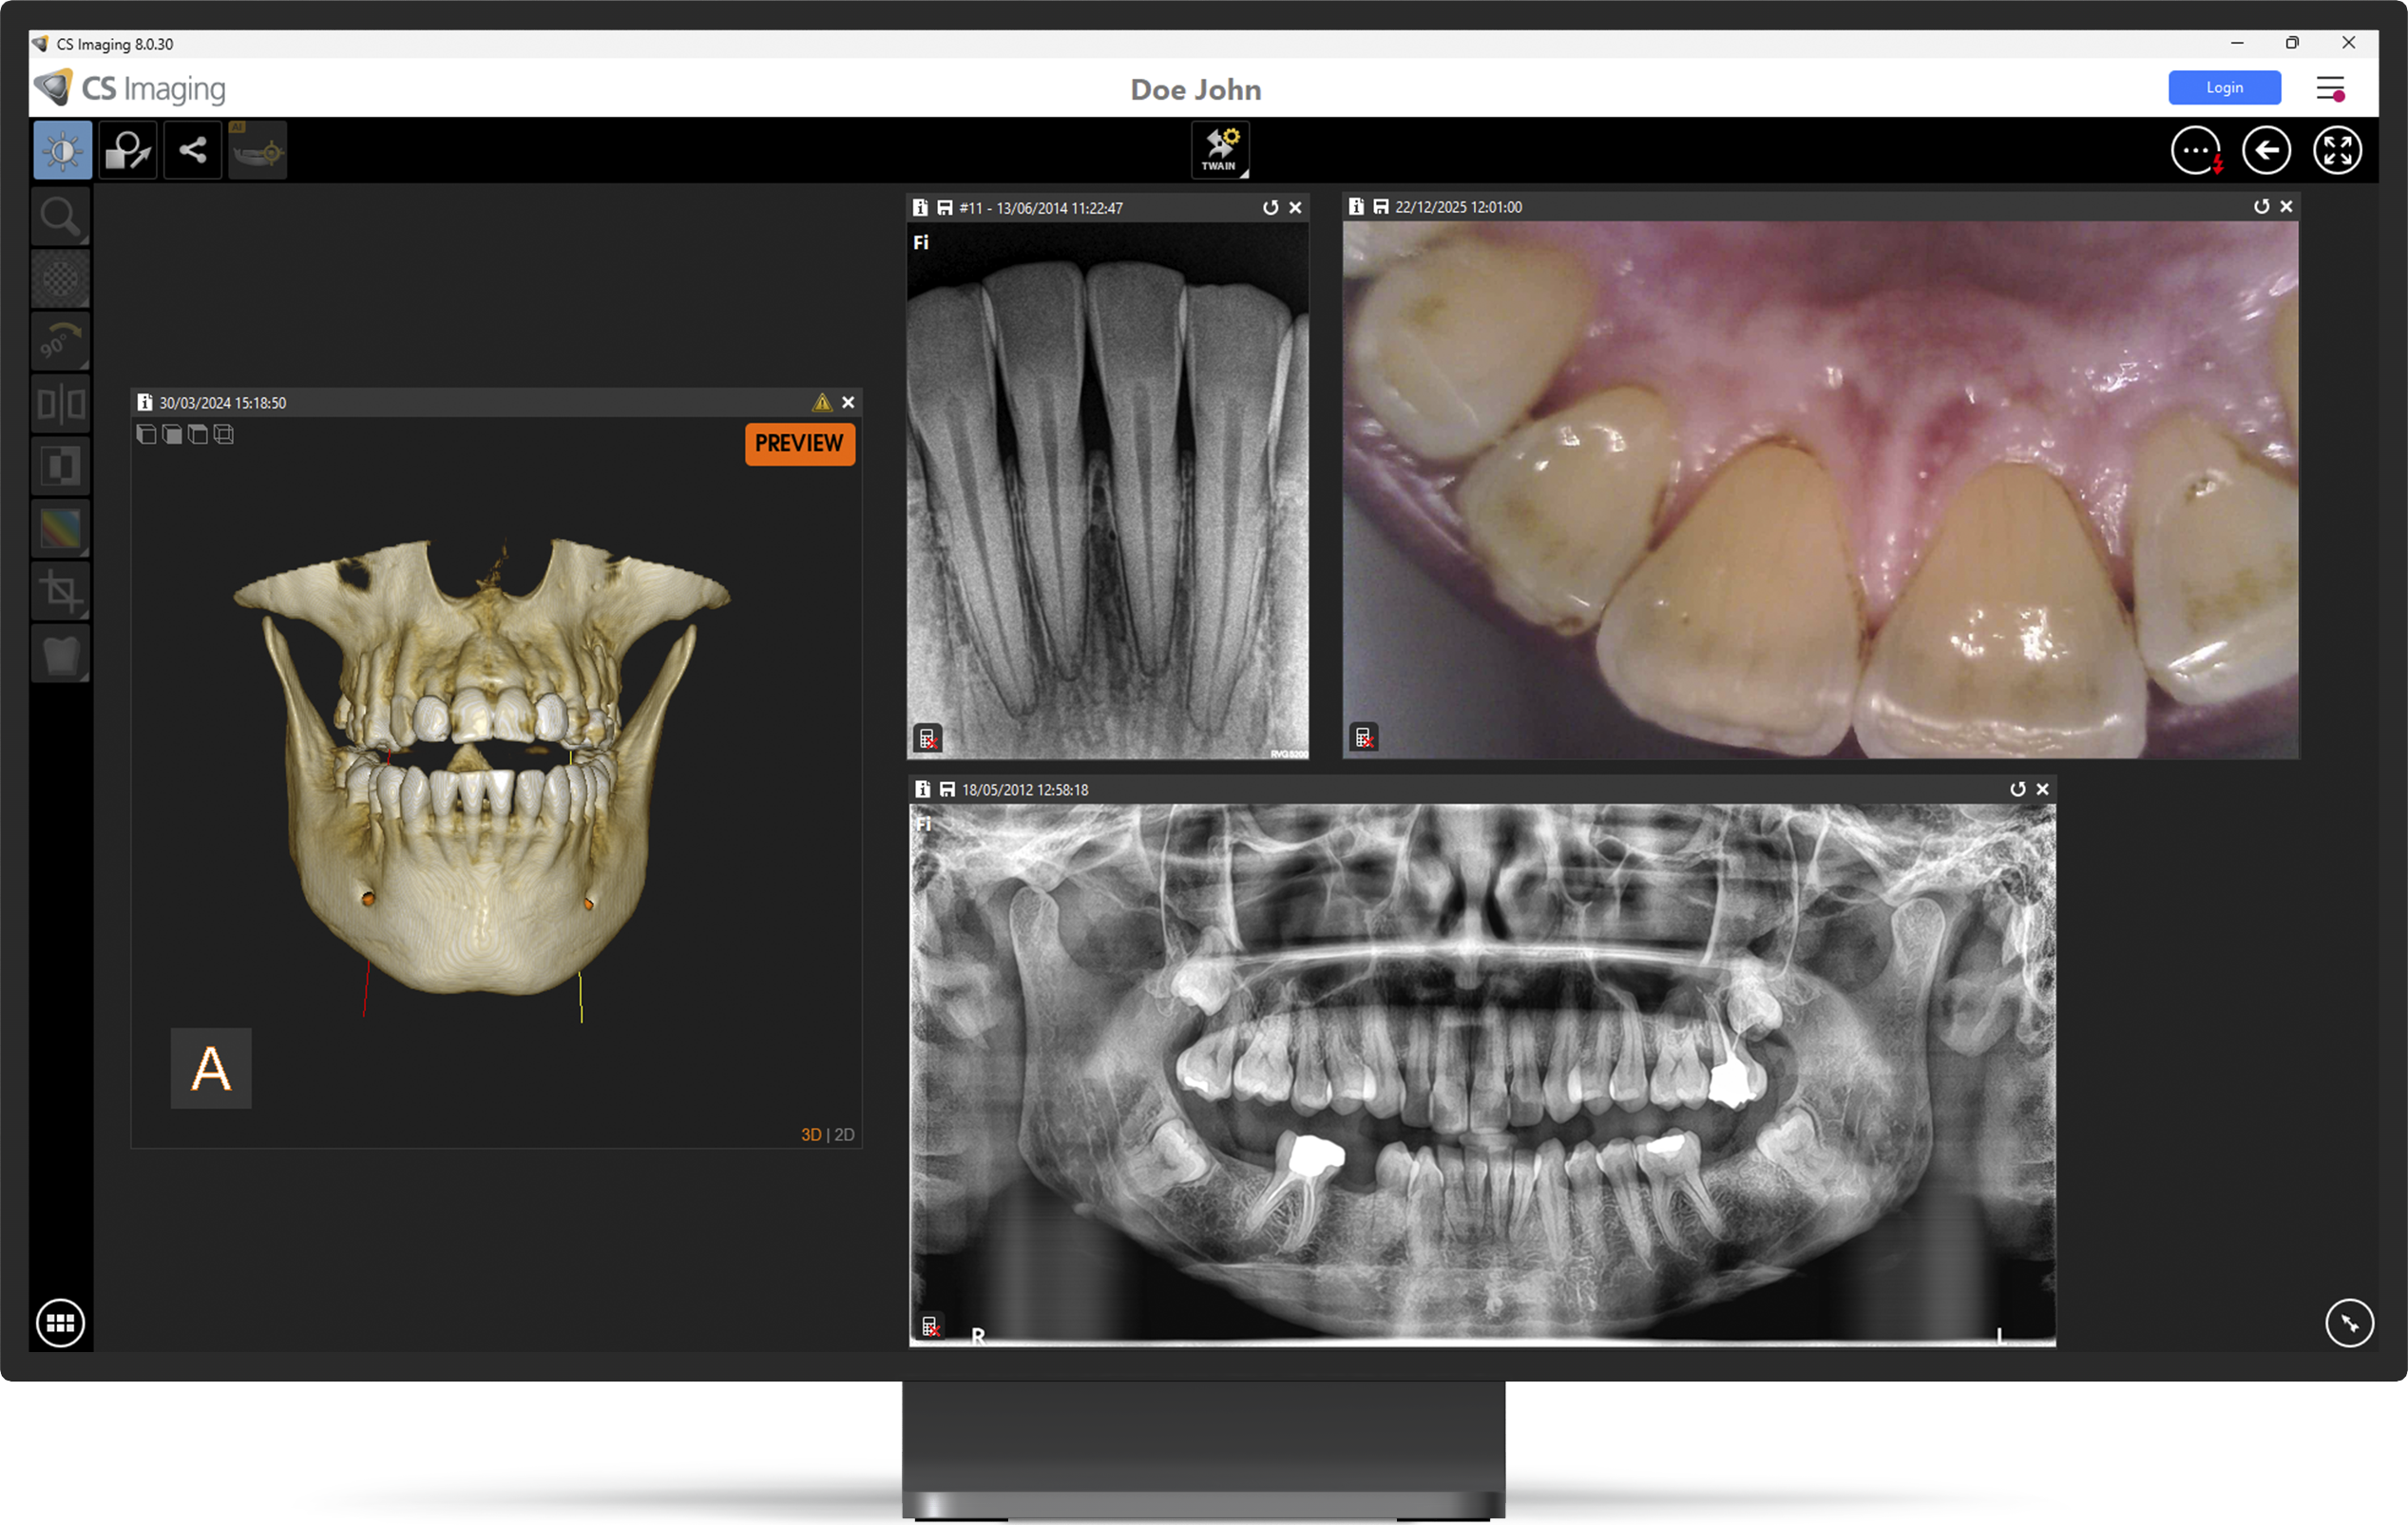

Στην εταιρεία μας λειτουργεί Showroom με τα μηχανήματα της Carestream Dental, των οποίων είμαστε εξουσιοδοτημένοι αντιπρόσωποι.